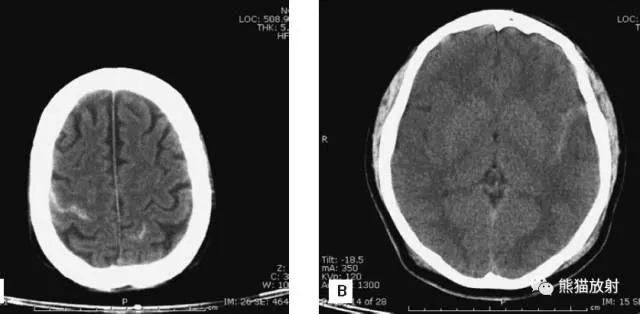

A:陈旧性脑梗死,右枕叶体积缩小;

B:左枕叶急性脑梗死,灰白质分界模糊,脑沟消失;

另一患者:

C、D:亚急性期脑梗死,低密度,无明显占位效应。

左侧大脑中动脉供血区脑梗死(亚急性期):

低密度,轻度水肿

缺血性脑卒中发作2-4天时,占位效应最明显。